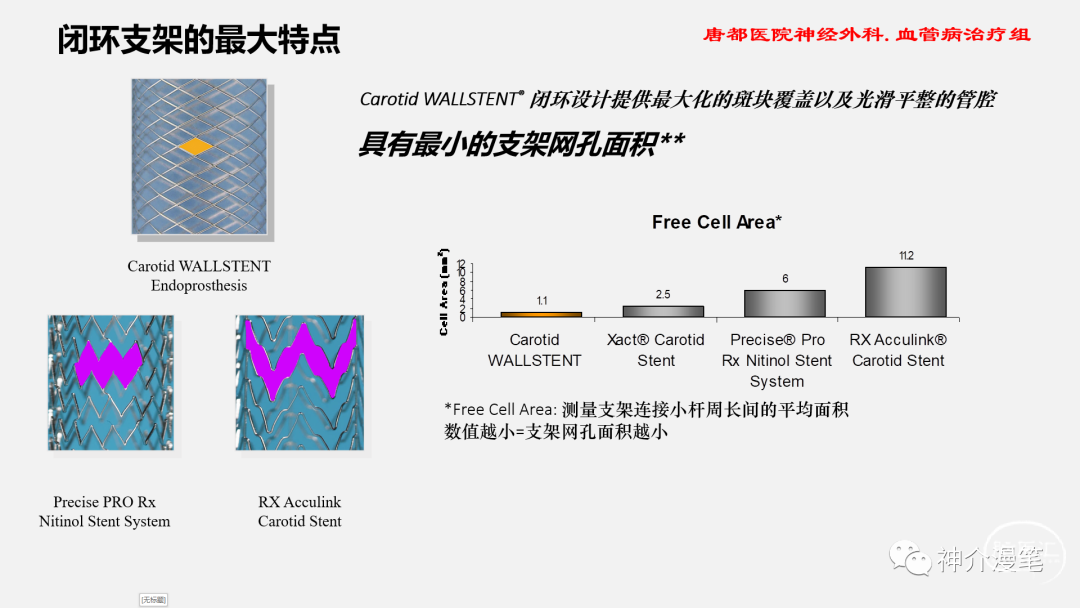

闭环支架的设计特点和开环支架刚好相反,所有的支架单元都呈现出连续封闭的状态,整个支架为一个连续完成的整体。其设计的特点使得其网眼更小,更利于提高局部金属覆盖率与对斑块的保护。但是其在迂曲血管的贴壁性会略差,同时因为其作为一个整体存在的特点,其趋势是使血管变直。因此对于血管走形的改变会略大。下图为闭环支架的设计特点,可以看到所有支架网格均为封闭连续的结构。

闭环支架更大的优势来源于更密更为紧凑的网孔设计,对于提高局部金属覆盖率,保护斑块脱落,特别是溃疡斑块,软斑块等有其独特的优势。此外对于串联病变,闭环支架具备更好的二次通过性,内壁更为光滑,很少出现导管通过困难等问题。因此对于对于串联病变,夹层修复,编织闭环更具优势。

Wallstent支架不同于前面两款,自身特点同样突出,关键词:编织支架,闭环支架,自膨支架,是目前主流颈动脉支架中唯一一款编织支架。具备着编织支架普遍共性,在不同管径血管内会被拉伸和短缩,释放难度略高于其他几款支架,但是有更高的金属覆盖率和更小的网眼面积。此外,wallstent支架的显影性是最棒的,这一点用过的可能都知道。